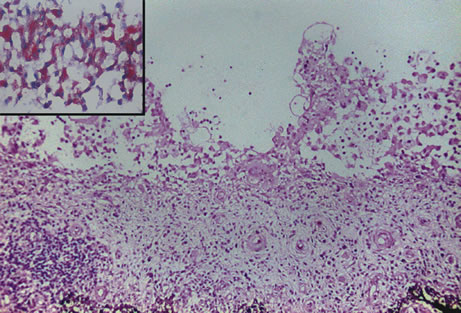

Inflammatory conditions may also lead to iris nodules. Patients suffering from fungal endophthalmitis may demonstrate an irregular yellow-white mass on the iris. Histologically, these appear as necrotizing granulomas containing mycotic agents (Fig. 2). In juvenile xanthogranuloma, a yellowish-gray iris lesion may be associated with spontaneous hyphema, and histopathologically the nodules demonstrate diffuse histiocytic infiltrate (Fig. 3). Multinucleated giant cells displaying peripheral foamy cytoplasm are also noted; these cells are known as Touton giant cells.29 The giant cells and the histiocytes contain lipid that can be demonstrated by oil red O stain.

Fig. 3. Juvenile xanthogranuloma. The iris is infiltrated by histiocytes, which form nodular aggregates on the anterior surface of the iris. (Hemotoxylin-eosin ×25.) Inset (×200) shows oil red O-positive histiocytes.